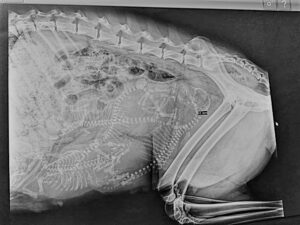

Per Röntgenaufnahme lassen sich Anzahl und Größe der Welpen bestimmen – man sollte erst um den 58./59.Tag röntgen.

Wir haben am 13.05. einen Röntgentermin ausgemacht für Gipsy.

59.Tag 13.Mai 2022

Heute Spätnachmittag war der Trächtigkeits Röntgentermin….so wie es aussieht wir es ein kleiner Wurf werden – wir haben ein

zählen können.